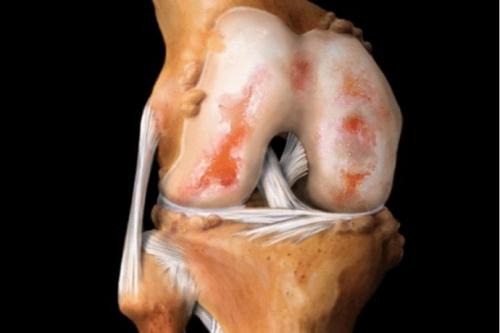

Так выглядит разрушенный хрящ.

Вид на поражённую хрящевую поверхность.